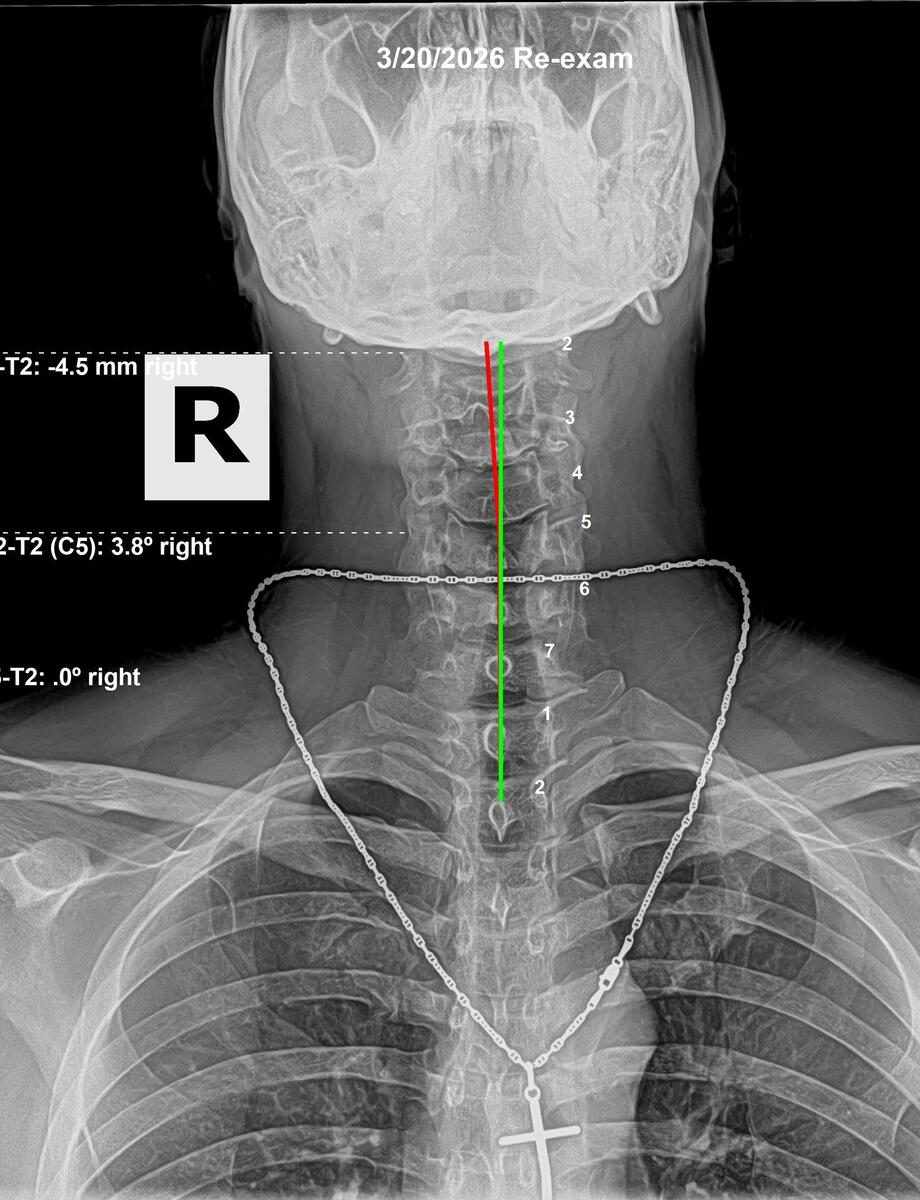

Follow-up cervical AP X-ray showing head tilt corrected to 0mm after 12 weeks of chiropractic correction, March 20 2026, Rochet Family Chiropractic Royal Palm Beach

After 12 Weeks — March 20, 2026

Cervical: Head tilt corrected from 2.7mm to 0mm. Subluxation at C2 corrected. Cervical vertebrae re-aligned.